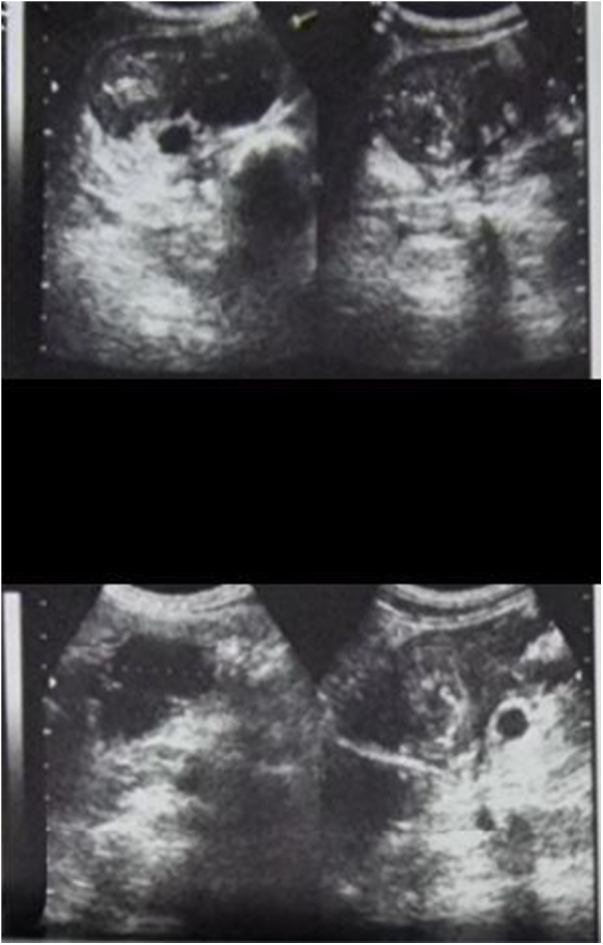

Case presentation: The patient presented with symptoms of abdominal pain, cramping, and significant bowel sounds, along with weight loss and a decreased appetite. Histopathological examination and upper endoscopy were used to diagnose the condition, and a gluten-free dietary treatment was implemented.